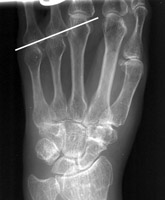

Diagnosis:Short 4th Metacarpal Discussion:Radiograph of the hand which reveals an abnormally short 4th metacarpal, as compared to the other metacarpal bones. Although this sign usually is associated with Turner's syndrome, the short 4th "metacarpal sign" carries a short differential diagnosis and is therefore not pathognomonic. References: